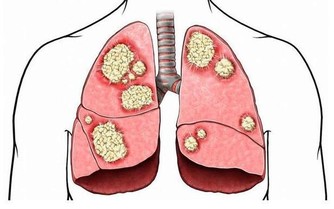

1、抽煙

萬萬沒想到吧。抽煙不僅僅傷害肺部,而且能直接損傷胃粘膜,損害胃的微血管,使胃黏膜長期處於缺氧狀態,最終導致慢性胃炎的發生。